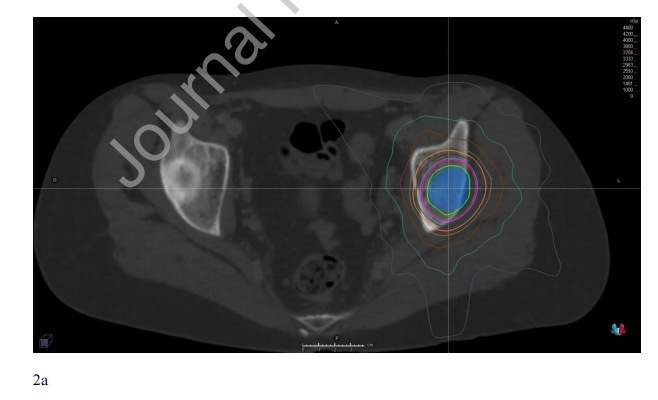

对于SBRT靶体积,没有标准的轮廓方法。具体来说,考虑到靶点解剖位置的异质性和肿瘤类型的放射敏感性,关于是否需要临床靶体积(CTV)扩大没有明确的指南。对于化疗后的骨靶区,可考虑采用COG入路,其总靶体积等于化疗后体积加上化疗前骨异常,CTV为解剖受限的1 cm体积外扩(NCT02306161)。对于完整的骨转移,可以考虑国际共识性的成人非脊柱骨转移CTV指南,对于完整的脊柱转移,也可以考虑国际脊柱放射外科靶体积勾画指南。然而,年轻患者的靶体积可能很复杂,并且某些特征如硬膜外疾病、脊柱旁疾病、靶体积大和软组织疾病可能会使患者面临较高的失败风险,因为靶区勾画存在挑战。在可行的情况下,建议使用多种成像方式,如CT、代谢成像(PET)和MRI;图2提供了一个示例。如果可能的话,放射肿瘤学家应该注意避免在骨骼不成熟的儿童中使用骨骺生长板,尽管应该避免损害肿瘤的覆盖范围。

图2。 (A)复发性尤文氏肉瘤左侧髋臼骨转移的15岁女性。病灶分5次给予40 Gy;PTV显示为蓝色。通过融合PET (B)和MR (STIR序列,C)定位转移灶。